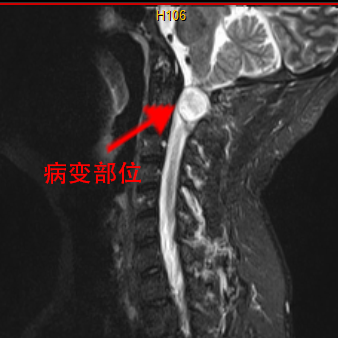

脊柱脊髓外科主任仇继任主任医师对罗先生的病情非常重视,为了查明原因,立即给罗先生完善了相关检查,并对罗先生的症状和体征进行详细分析。各项检查回报后证实了仇继任的考虑,患者第1颈椎椎管内长了一个肿瘤,且位置非常贴近脑干延髓生命中枢,由于特殊解剖生理特点,此处的肿瘤易并发四肢瘫痪和呼吸功能障碍,甚至危及生命。该部位的手术难度大,操作技术要求高,术中处置不当极易导致患者呼吸心跳停止,因此在治疗上存在较大的困难。

为了解决罗先生颈椎上的“定时炸弹”,缓解肢体麻木、行动不便的问题,仇继任及其团队针对罗先生的病情结合术前CT、MRI等影像资料,对治疗方案进行反复讨论和研究,制定了最佳的手术方案——显微镜辅助下精准切除高位颈椎椎管内肿瘤手术。

术中增强MRI

经过充分的术前准备,仇继任及其团队如期为罗先生进行手术。手术过程中发现肿瘤组织与延髓神经组织粘连紧密,手术难度进一步增大。凭借着精湛而熟练手术技巧及默契的团队配合,仇继任在显微镜下仔细分离肿瘤与脊髓神经组织、精确止血。经过2小时的紧张奋战,手术顺利结束。术后在科室全体医护人员的精心护理下,患者右侧下肢疼痛、麻木症状明显缓解。由于术中未破坏关节突关节,脊柱稳定性得到大部分保留,罗先生术后很快便能起床活动,术后1个星期出院,1个月后随访恢复良好。